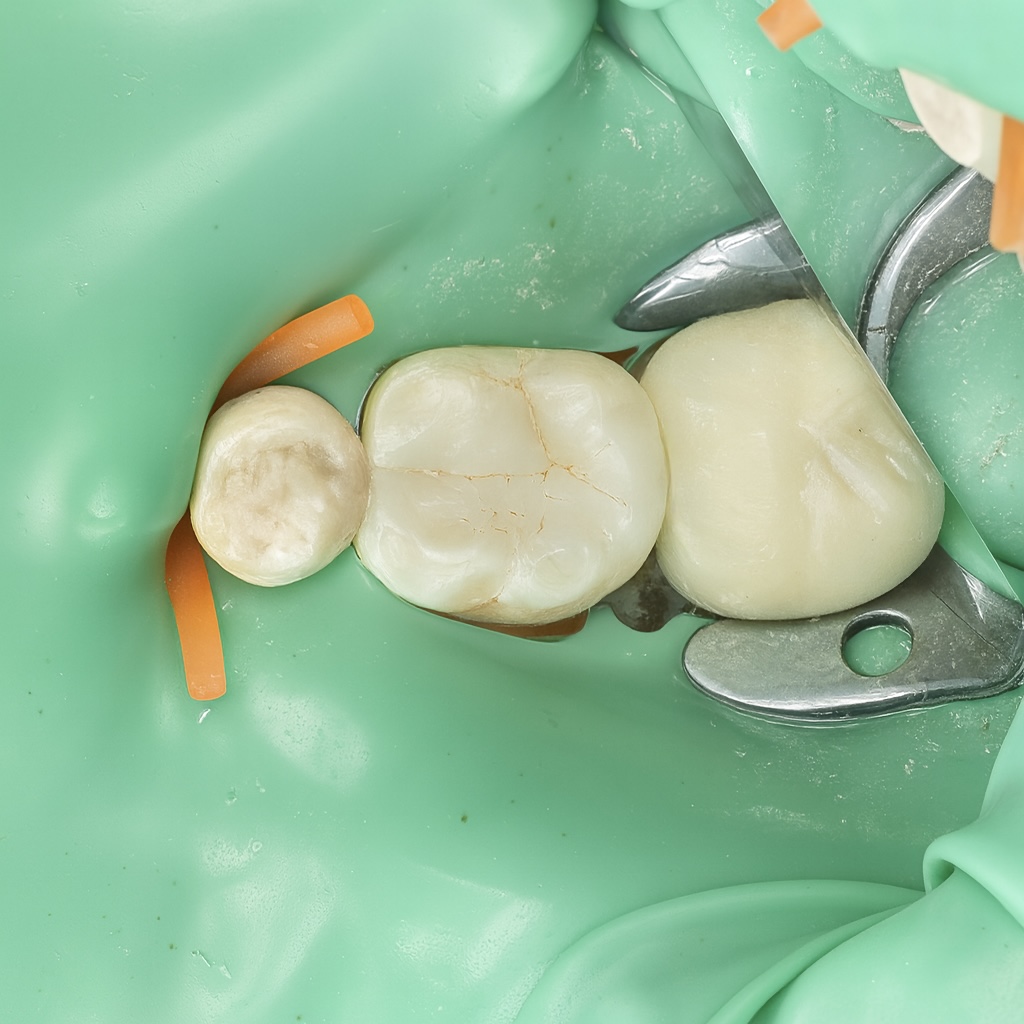

5. Cuspal Coverage / Composite Onlay

- Enamel cleaned and selectively etched.

- Universal adhesive applied following manufacturer protocol.

- Cuspal reconstruction done anatomically.

- Occlusal anatomy built cusp-by-cusp, guided by natural morphology.

6. Finishing & Polishing

- Pre-polish: Enhance / Pogo system (Dentsply)

- Staining: Tokuyama Estelite Ocher stain for fissure warmth

- High gloss: 3M Easy Match polishing sequence

- Final glossy finish: Lucida (StyleItaliano) + Diashine